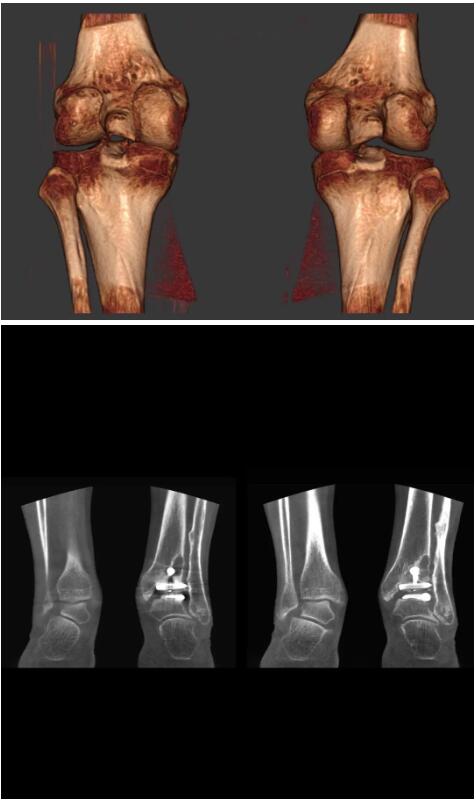

而患者站著做足部或者踝部做CT檢查還有個(gè)好處是,可以檢查患者在負(fù)重的情況下,骨關(guān)節(jié)的真實(shí)情況,而躺著做CT掃查時(shí)未必能看出來。負(fù)重CT掃查特別是對于受傷的運(yùn)動員或者舞蹈員來說意義更大,能夠更準(zhǔn)確地評估傷情,幫助他們盡早復(fù)原。

以上介紹的CT均來自國外同一家公司,這些CT均配置了可視化軟件,可以進(jìn)行切片、3D重建以及大型CT附帶的所有典型的操作功能。

以下是這些“特立獨(dú)行”的CT所拍出來的圖像: